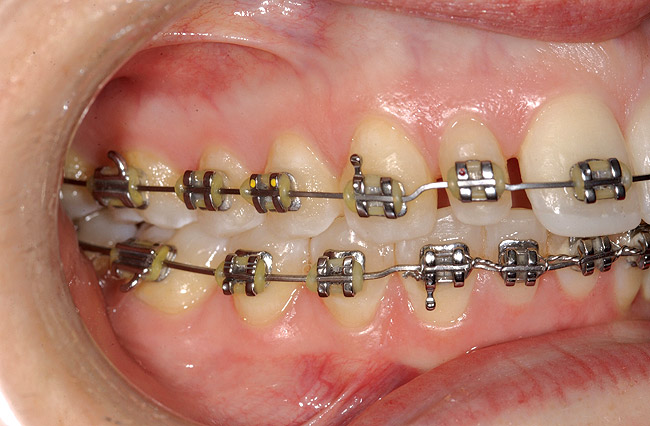

Figure 9  Orthodontic distraction osteogenesis to develop the implant site of tooth No. 23.

Figure 9

Figure 12  Right buccal view showing posterior occlusion established, canine guidance and proper space appropriation around peg lateral tooth No. 7, and intruded worn incisors.

Figure 12

This treatment plan was elected with the premise to reevaluate treatment options during orthodontic tooth movement. Soft-tissue augmentation was initiated to correct the mucogingival defect in the area of teeth Nos. 21 and 22. A free gingival graft was performed to achieve an adequate band of attached and keratinized gingiva to resist potential stripping on the root surfaces of teeth Nos. 22 and 21 during orthodontic movement (Figure 8). Orthodontic movement then was initiated to site-develop position No. 23 for an implant (Figure 9 through Figure 11). Orthodontics also was used to idealize the patient’s occlusion and develop canine guidance to minimize occlusal load and maximize the redistribution of forces36-40 for protecting the future implant from deleterious forces. The space was opened around the peg lateral tooth No. 7, and the gingival levels were aligned for maxillary incisors. Bonding was performed to restore the length of teeth Nos. 8 through 10 and to bond the peg lateral to a normal tooth form, which allows the orthodontist to idealize the posterior occlusal scene and maintain canine guidance (Figure 12 through Figure 13).